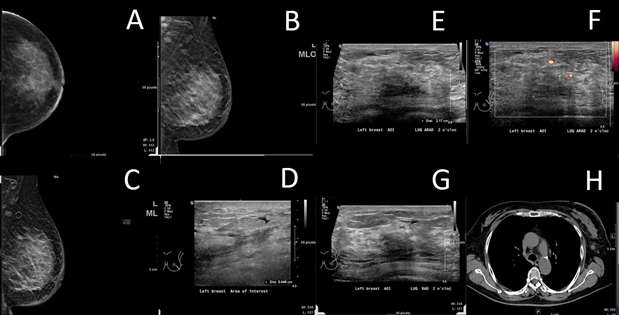

Breast metastasis from melanoma to an intramammary lymph node 5 years after the initial tumor was identified:

Case: Metastasis to the Breast From a Non-breast Primary Cancer Figure 2

Figure 2: (A-B) On spot MLO and MLO mammogram images respectively, there is a mass, measuring 6 mm in the right breast, at 12 o'clock, in the upper outer quadrant. (C-F) Ultrasound demonstrates an intramammary lymph node measuring 6 x 7 x 4 mm in the right breast at 12 o'clock, upper outer quadrant located 0 centimeters from the nipple. This correlates with the mammographic finding. No axillary lymphadenopathy was identified.